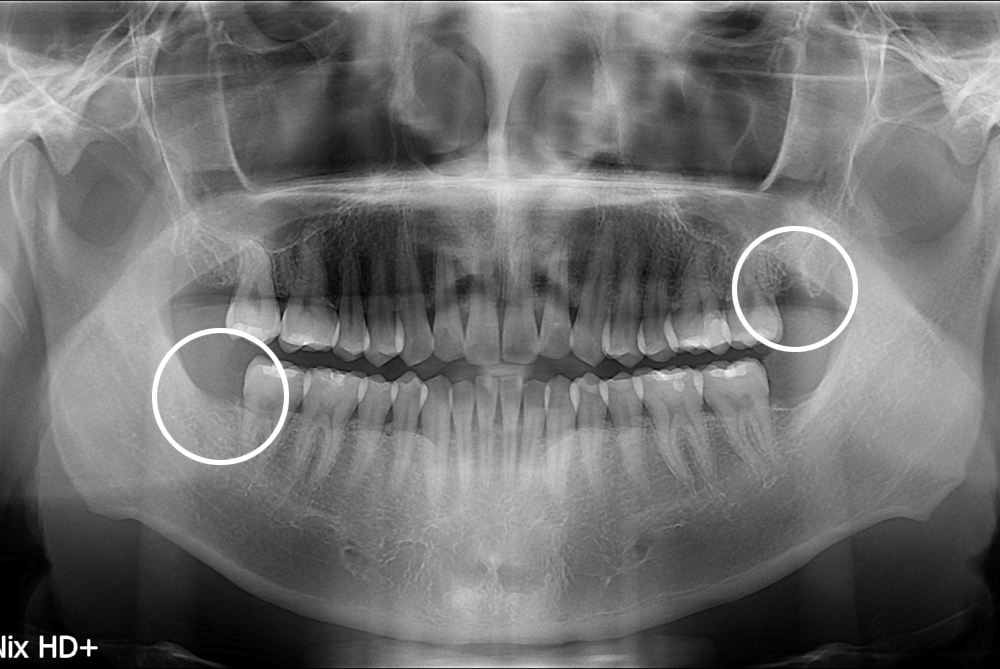

치료후 : 2017-02-22

세종치과는 구강악안면외과학 박사이신 원장님이 발치하는 치과입니다.